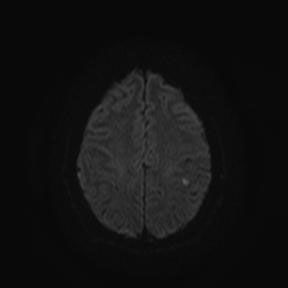

Магнитно-резонансная томография (МРТ) - наиболее предпочтительный метод в определении локализации, а главное - в оценке стадии развития ишемического процесса. В острую фазу наибольшую информацию несут диффузионно-взвешенные изображения (сокращенно: ДВИ) - изображения, полученные с помощью специализированной импульсной последовательности, предусмотренной в МР-томографах экспертного класса, которую мы применяем при исследовании всех без исключения пациентов.

При использовании ДВИ можно увидеть минимальное изменение диффузии (скорости движения) жидкости в мозговой ткани на молекулярном уровне, что является первым признаком ишемического повреждения головного мозга. Кроме того, при исследовании головного мозга у пациента с подозрением на лакунарный инфаркт (как и во всех других случаях) мы применяем весь набор импульсных последовательностей, соответствующий международному стандарту, для выявления возможных сопутствующих изменений.

При сканировании головного мозга в нескольких режимах в кортикальных отделах левой теменной доли был обнаружен лакунарный инфаркт диаметром 7мм. Острый инфаркт хорошо виден на ДВИ (импульсная последовательность, доступная в томографах экспертного класса), но плохо виден в режиме с подавлением сигнала от свободной жидкости.